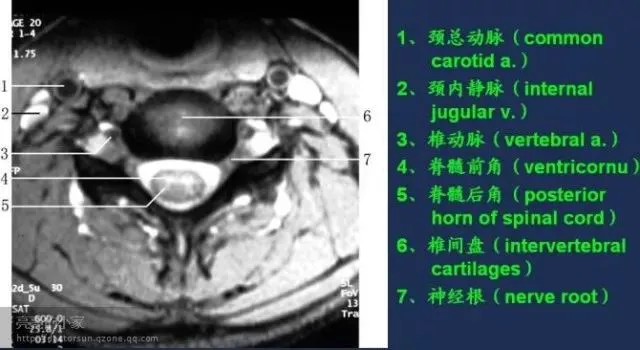

收藏!全身MRI解剖图谱,医生必备